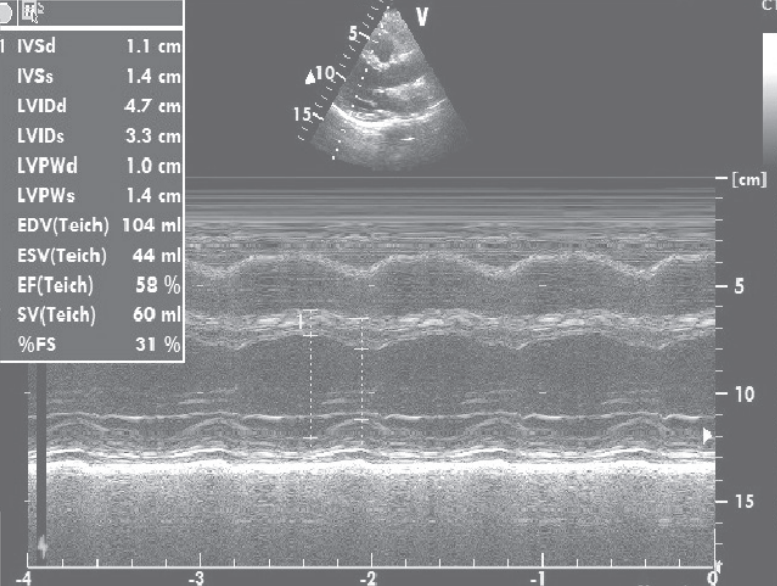

心脏超声:左心室扩张,左心室舒张末期内径57 mm,左心室收缩末期内径51 mm,左心室弥漫性运动减弱,LVEF=15%;限制性舒张功能障碍(E/E‘=19),二尖瓣、三尖瓣反流,中度肺动脉高压(图2)。

图2 心脏超声结果

先后予葡萄糖酸钙、乳酸钙(6000 mg/d)、骨化三醇(0.5μg/d)治疗,低钙血症逐渐纠正,1个月后LVEF恢复至30%,NYHA心功能II级。继续补钙治疗,1年后调整每日用药为“乳酸钙3g、α-钙剂2μg、卡维地洛12.5 mg、左甲状腺素150μg”,复查心脏超声,左心室舒张末期内径47 mm,左心室收缩末期内径33mm,LVEF 58%(图5)。

图5 复查心脏超声